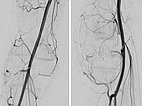

Die digitale Subtraktionsangiographie (DSA) des Knies (links a.-p. Projektion, links seitliche Projektion) zeigt eine AVM mit einem eher kugeligen, aneurysmatischen Nidus sowie einen weiteren Nidus intraossär im lateralen Tibiaplateau. Dieser sehr kugelige, aneurysmatische Nidus zusammen mit der schmerzhaften, progredienten Raumforderung lässt an ein PTEN-Hamartom denken.